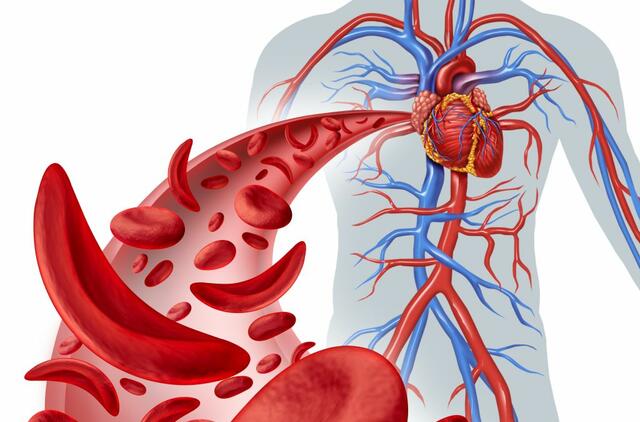

„Tokiu atveju viskas, ko reikia norint užkirsti kelią ligai, yra paciento sąmoningumas ir atsakingas požiūris į savo sveikatą. Būtina atidžiai sekti tokius rodiklius kaip kraujo spaudimas bei cholesterolis.

Mat padidėjusio cholesterolio nekontroliavimas – tai tiesus kelias į aterosklerozės vystymąsi, o toliau jau pasekmės – išeminė širdies liga, miokardo infarktas ar insultas“, – aiškina gydytojas K. Bumblauskas.

Jei vien gyvensenos pokyčiais sureguliuoti cholesterolio koncentracijos kraujyje nesiseka, taikomas medikamentinis gydymas statinais.

Moksliniais tyrimais įrodyta, kad ilgalaikis cholesterolį mažinančių vaistų (statinų) vartojimas gali sumažinti tikimybę susirgti širdies ir kraujagyslių ligomis.

Sumažinus blogojo cholesterolio kiekį organizme, smulkiosiose kraujagyslėse esančios aterosklerozinės plokštelės apsaugomos nuo plyšimo, sumažinama trombų susidarymo rizika.